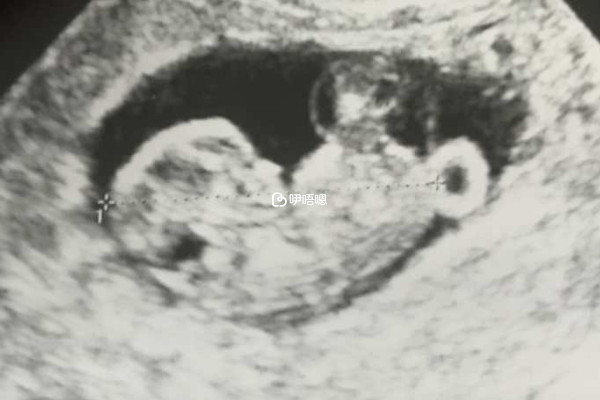

生男孩生女孩一直以來都是各位孕媽媽討論最多的問題,但其實自然規律的生男生女本就五五分,也不可能預測還沒懷孕之前就能知道生男生女,懷孕後雖然可以通過B超來看男女,但是在我國是違法的,所以民間現在還流傳了很多的懷孕前生男生女的方法,下面就列舉了一部分: